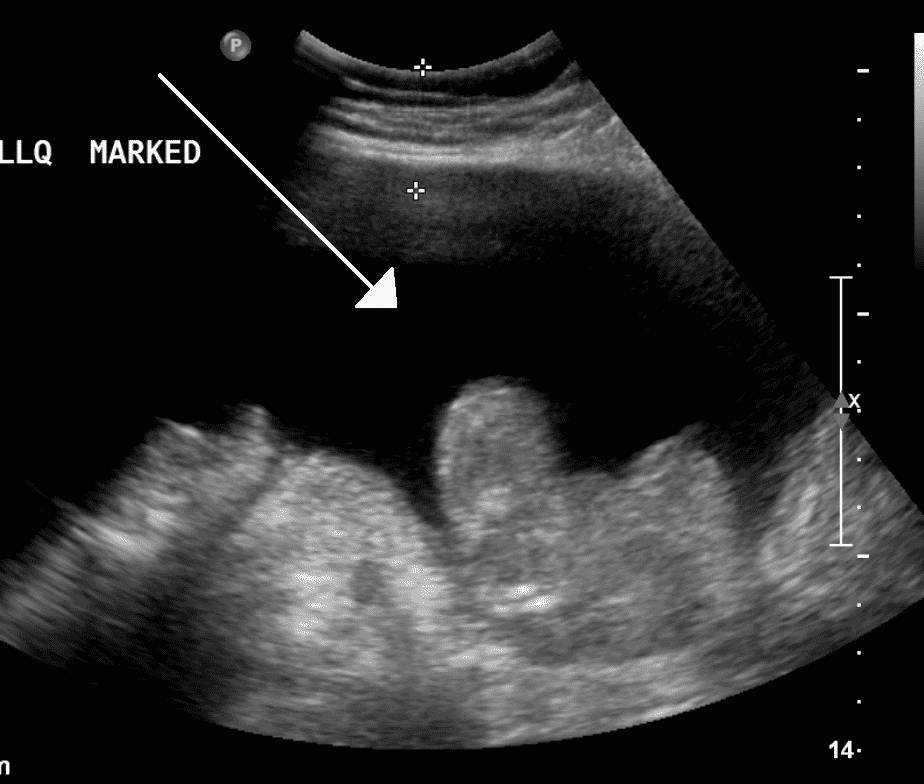

- Ультразвуковое исследование органов брюшной полости (УЗИ);

УЗИ органов брюшной полости дает возможность выявить выпот от 100 мл, определить состояние внутренних органов, выявить или исключить другие возможные патологии.

При сердечной недостаточности, можно обнаружить расширение нижней полой вены. Этот метод является наиболее простым и информативным.